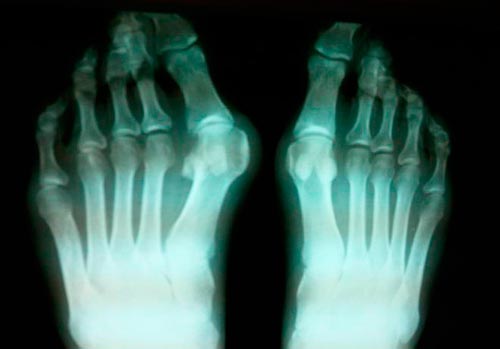

Рентгенологическое исследование на поздних сроках развития заболевания

Этот метод исследования активно используется при установлении диагноза. Исследованию подвергаются суставы кистей рук и стоп. Поражение большого пальца ноги рентгенологическим исследованием дает врачу картину состояния костей и хрящей. На руках тофусы будут заметны при хроническом характере болезни.

Компьютерная томография позволяет при помощи серии точных рентген снимков провести качественное исследование. При этом с высокой точностью определяется степень деформации сустава и локализация зоны воспаления. Даже на начальном этапе болезни будут видны уплотнения тканей возле сустава. Рентгенологическое исследование необходимо для определения диагноза и исключения вероятности развития других заболеваний, которые тоже могут поражать суставы.